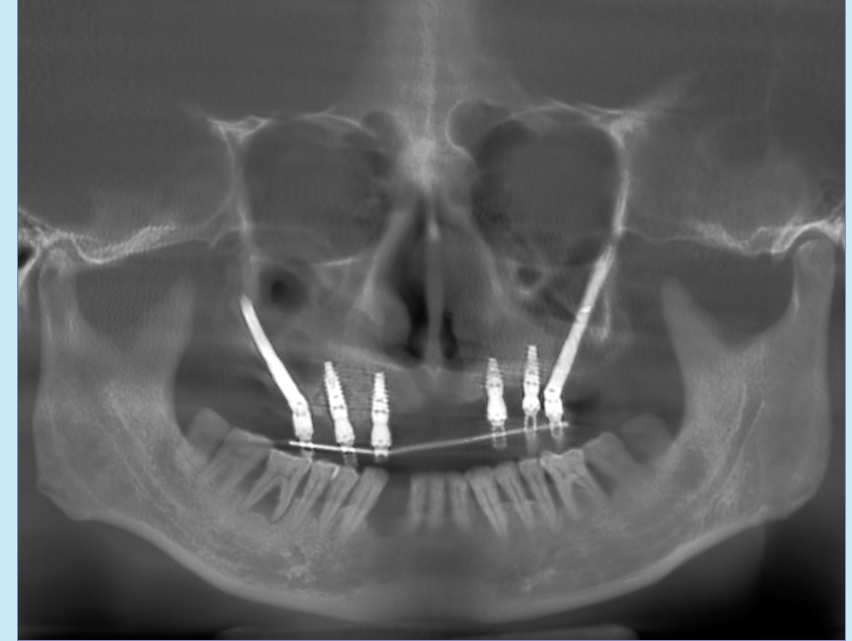

我们团队通过数字化三维设计软件规划种植,并由团队自行设计生成数字化种植导板,对术中可能出现的各种情况进行了充分的术前准备。凭借过硬的技术和丰富的临床经验,冯智强博士在患者颧骨两侧植入2颗穿颧种植体,配合在前牙区植入4颗种植体,当天戴牙修复固定假牙,即完成上颌半口种植。

术后拍片图